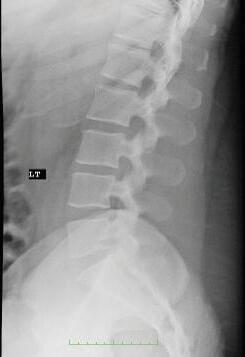

FIGURE 1-5 Left lateral radiograph of the lumbar spine. In lateral views the side indicator (LT) indicates the patient’s side closest to the x-ray detector.